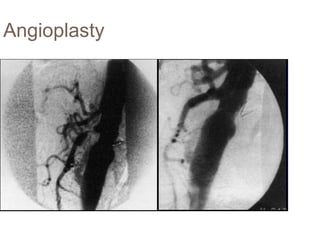

Angio/CTA

Angioplasty